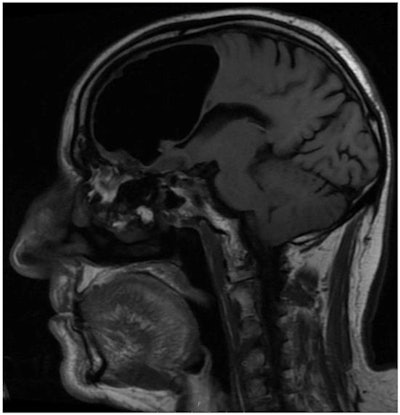

Hoping to clarify the cause of the man's symptoms, the researchers turned to imaging. They acquired CT scans of the brain and found a 3.5-inch air-filled cavity, or pneumatocele, within the patient's right frontal lobe (BMJ Case Rep, February 27, 2018). Additional MR images of the head corroborated that the hypodense spot was, indeed, an air pocket and also uncovered an osteoma and signs of acute ischemia nearby.

Collectively, the findings suggested that the osteoma had gradually eroded the bone plate near the nasal cavity enough to allow air to enter the right frontal lobe in a "one-way valve effect."